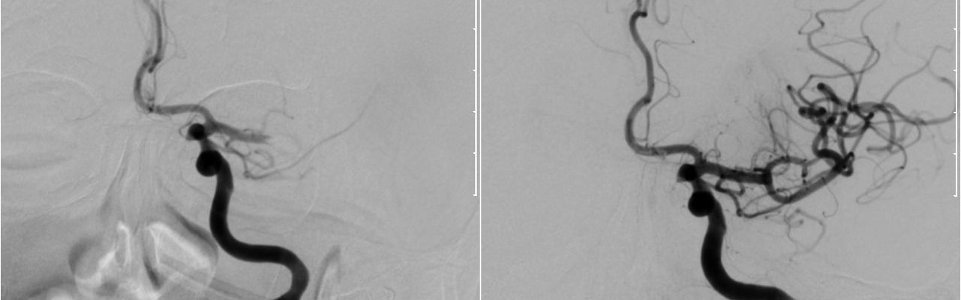

Eine Darstellung der Blutgefäße im Gehirn vor (links) und nach (rechts) der Thrombektomie.

Betrifft der Verschluss die Basilaris-Arterie, führt der Schlaganfall fast immer zum Tod, da dieses Gefäß für die Versorgung des Hirnstamms zuständig ist. Die einzige Chance in diesem Fall ist die Thrombektomie. Bei der Thrombektomie wird ein dünner Schlauch von der Leiste in die große Halsarterie eingeführt. Durch diesen wird ein zweiter Katheter, an dessen Ende sich ein Stent befindet im Gerinnsel entfaltet. Dadurch wird die Durchblutung des Gehirns wieder hergestellt. Durch Entfernen des Stents in geöffnetem Zustand wird das, sich im Stent befindliche Gerinnsel mitentfernt, wodurch eine dauerhafte Durchblutung des Gehirns gewährleistet wird. Ähnliche Verfahren kommen auch bei der Behandlung eines Herzinfarkts schon sein längerem zum Einsatz. Es kann auch ein röhrenförmiges Metallgitter eingesetzt werden, damit die Arterie dauerhaft offen bleibt. Der Eingriff wird in Vollnarkose durchgeführt und dauert etwa eine halbe Stunde. Mit seinen erfahrenen Oberärzten stellt Prof. Rath sicher, dass dieses Verfahren jederzeit durchgeführt werden kann.